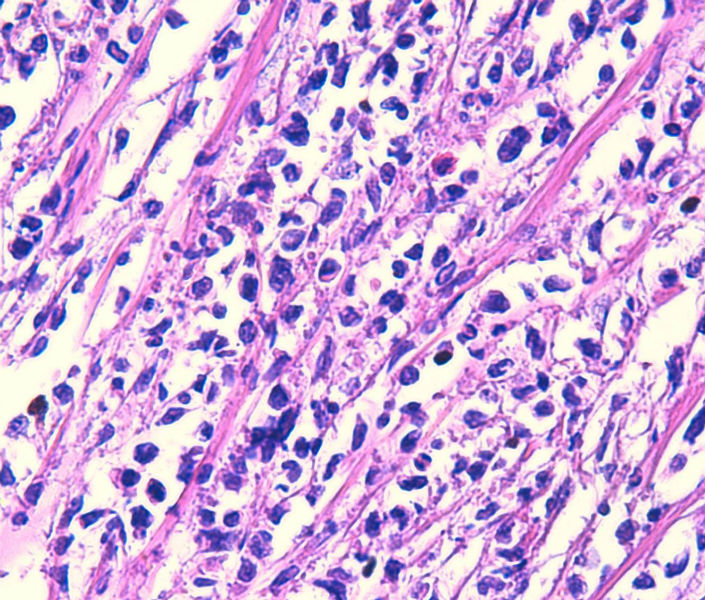

免疫组化染色:CA125(-),PLAP(-),NSE灶状阳性,Vimentin(+),a-inhibin(-),CK7(-),CK20(-),CD15(-),PSA(-),S100(-),MyoD1(-),CD38(-),CD56(-),HMB45(-),CK8(-),NF(-),CGA(-),syn(+),MPO散在(+)可能是炎细胞吧,LCA(+),CD133(+).

好的HE切片和准确可靠的免疫组化结果是淋巴瘤等较难病例病理诊断的基础。本例从HE来看不太像典型的淋巴瘤或癌,免疫组化就很重要了,但本例组化结果之间似乎不易解释:

1.syn与LCA等淋巴系标记的阳性判断,镜下须观察阳性细胞是否一致,是相同的细胞还是不同的细胞等

2.如果考虑淋巴瘤,B系的标记如CD20和PAX5结果也不太一致,另外CD133+究竟如何也有待探讨,好像楼主未显示其图片

3.ALK等也不太确切,

不知楼主以上的组化结果阴阳性对照如何?我个人经验不足,不敢妄下结论,但认为诊断淋巴瘤(弥漫大B,或间变淋巴瘤)可能会有风险。

今天又做了免疫组化,请大家帮看看。CD10(-),CD138(-),CDX2(-),CD3(-),CyclinD1(-),CD2(-),CD117(-),CD7(-),CD30(-),CD23(-);CD20强(+),BCL-2,Bcl-6,EMA,PAX-5,MUM-1,CD5,ALK,CD68都是散在阳性,大家帮确定一下是否阳性。B细胞淋巴瘤可以确定了,不知是哪种类型的?

是的,syn(+),LCA(+), CD79a阳性, CD3阴性,NSE是局部胞核,胞浆着色,主要是胞浆着色;SYN也是局部,主要是胞核着色,胞浆很少。不对吗?我也迷糊。也许我看错了,不像那种典型的胞浆颗粒状着色。大家帮看一看。